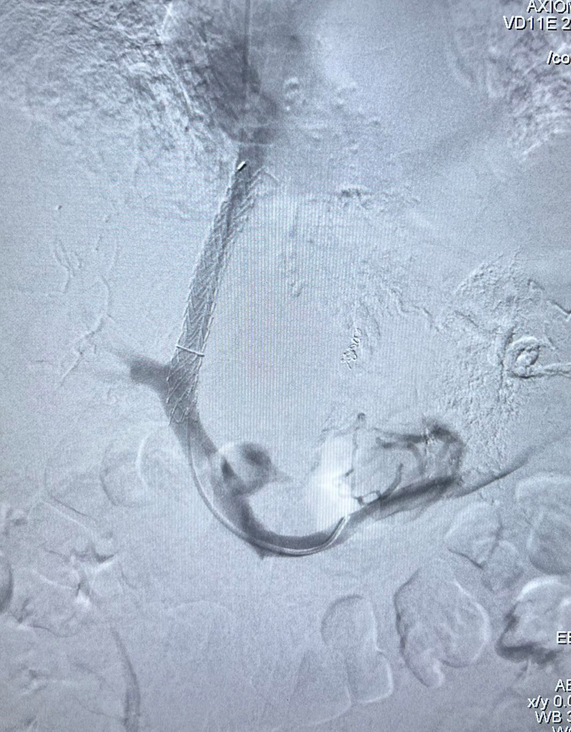

急诊 TIPS 应用

对于内镜反复止血失败的急性上消化道大出血患者,TIPS 可作为救命手段。我们曾接诊术中持续呕血的危重患者,通过急诊 TIPS 成功止血。

急性上消化道大出血急诊TIPS

多次内镜止血无效,急诊DIPS